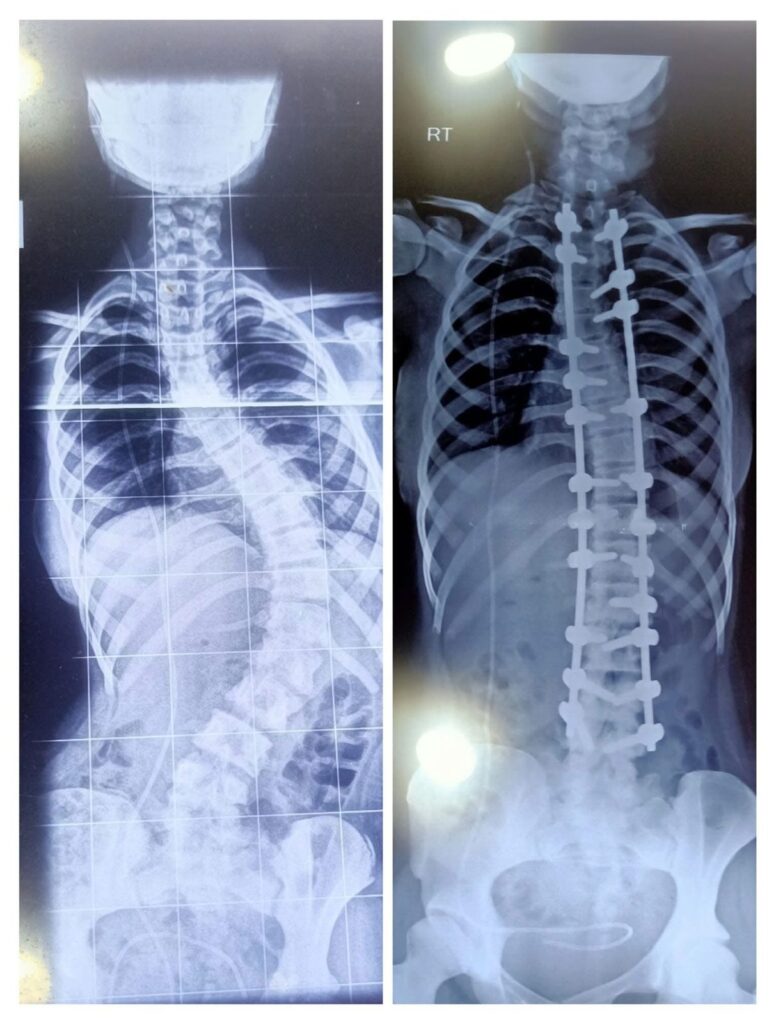

X-rays are used to confirm the diagnosis and to measure the severity of the curvature using the Cobb angle. Curves less than 20 degrees are generally classified as mild, those between 20 and 40 degrees as moderate, and curves greater than 40–50 degrees as severe.

The procedure typically involves:

- Placement of titanium screws in vertebrae

- Connecting the screws with rods to correct alignment

- Correcting the deformity with controlled manoevers

- Bone grafting to achieve spinal fusion

Fusion stabilises the spine and prevents further worsening of the curve.